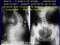

rozdzielczość: 800 x 600